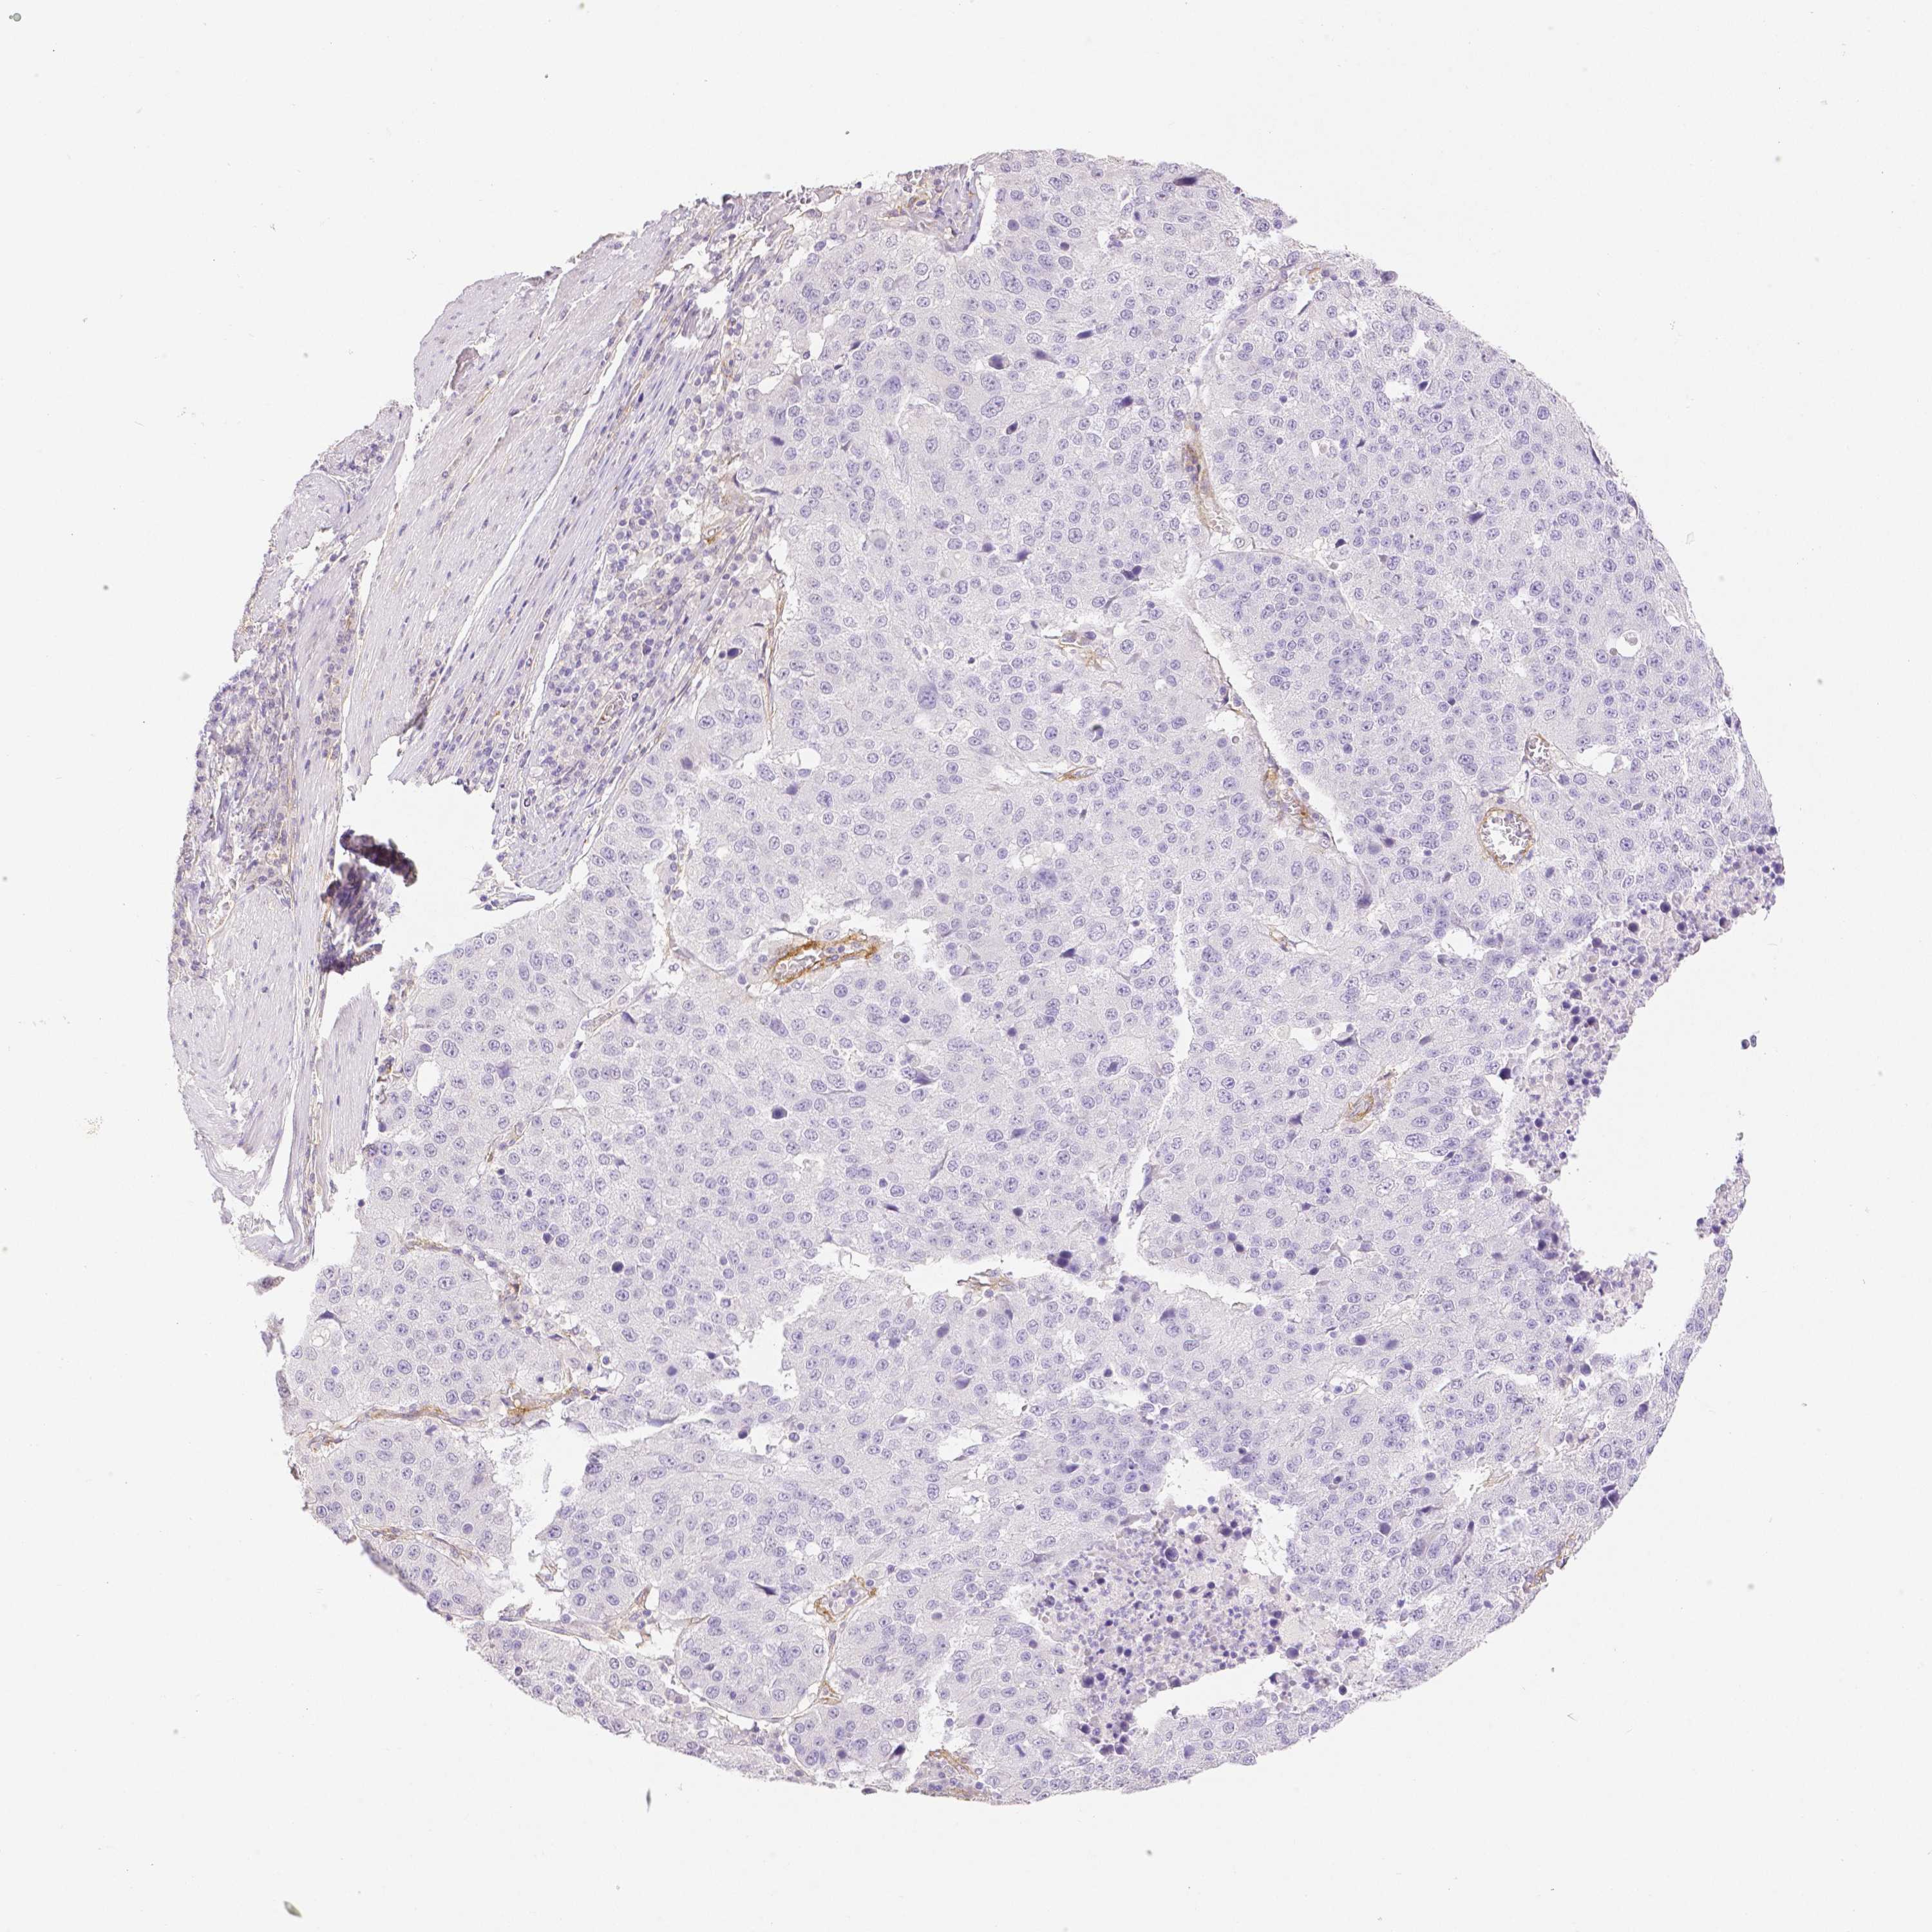

STOMACH CANCER - Protein expressioni

A mouse-over function shows sample information and annotation data. Click on an image to view it in a full screen mode. Samples can be filtered based on level of antibody staining by selecting one or several of the following categories: high, medium, low and not detected. The assay and annotation is described here.

Antibody stainingi

Antibody staining in the annotated cell types in the current human tissue is reported as not detected, low, medium, or high, based on conventional immunohistochemistry profiling in selected tissues. This score is based on the combination of the staining intensity and fraction of stained cells.

Each image is clickable and will lead to virtual microscopy that enables deeper exploration of all samples and also displays staining intensity scores, fraction scores and subcellular localization as well as patient and tissue information for each sample.

Antibody HPA003733

Antibody CAB068243

Antibody CAB068244

Staining

High

Medium

Low

Not detected

Intensity

Strong

Moderate

Weak

Negative

Quantity

>75%

75%-25%

<25%

None

Location

Nuclear

Cytoplasmic/membranous

Cytoplasmic/membranous,nuclear

Adenocarcinoma, NOS